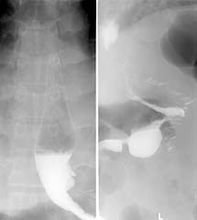

手術併發症發生幾率低,但要萬一發生併發症將會相當嚴重。胃切割位置滲漏發生率,如發生病人住院時間可能會較長(以月計),部份病人需要再做手術或植入支架修補。